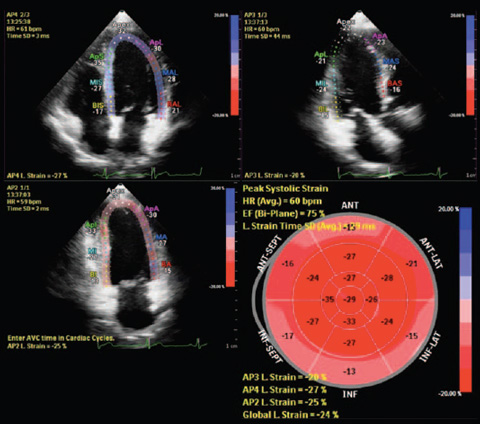

Функция интеллектуального определения анатомических структур изучает данные УЗИ пациента и применяет адаптивную интеллектуальную логику системы с использованием трехмерных анатомических моделей для создания более простых и воспроизводимых результатов. Инструменты интеллектуального определения анатомических структур, например HeartModel, используют усовершенствованное моделирование органов, формирование срезов изображений и надежный количественный анализ, помогая упростить проведение УЗИ, обеспечивая более высокую воспроизводимость, предоставляя при этом клиническую информацию нового уровня для решения экономических и клинических задач, возникающих в условиях современного медицинского учреждения.

Инструменты интеллектуального определения анатомических структур превращают изображения в ответы